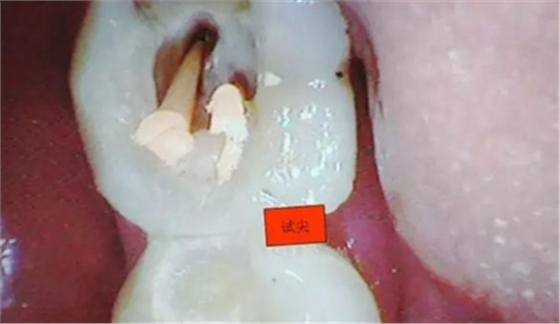

圖四

開髓完后,總覺得是不是牙體量去多了,拍片給人這種直觀感覺。

3.開髓去腐后,髓腔基本就是這樣,在頰側(cè)近遠中都有根管口顯示,初步用8號C+銼去試探性探查根管,沒有阻力感,以為就是c型根管,舌側(cè)用C+銼時有阻力感覺,接上測量儀去探查根管,以防C+銼探通后超出根尖孔,最后舌根長度16mm*15號K銼(16.5mm*8號C+銼),機擴F2。接下來著重頰側(cè)的根管尋找,后來在頰側(cè)近遠中插入K銼時總覺得K銼尖段都指向一個位置,感覺不對,再次讀X線片,后來發(fā)現(xiàn)術(shù)前沒有仔細查看X線片,以及未回顧這位患者年齡,也就忘記牙齒的增齡性改變的含義。髓腔之所以小或者不清楚,一個因為年齡增加的原因二是因為牙齒長期受到外界物理化學刺激所導致髓腔變小,甚至沒有髓腔顯影。本病例患者,髓腔有大概顯影,但髓室里好像有增生的牙體組織,其實就是髓石。并且和髓室底相連接。如果不注意,有可能按常規(guī)預備方法進行預備。

4.接著與患者溝通后,同意繼續(xù)去除髓石,用細小的安全端金剛砂車針輕微的去除,沿著弧形方向切割,去除后發(fā)現(xiàn)不是2個根管口,而是一個根管口,有點類似下頜6遠中根管口的樣子。(遠中頰根16mm*15號K銼)